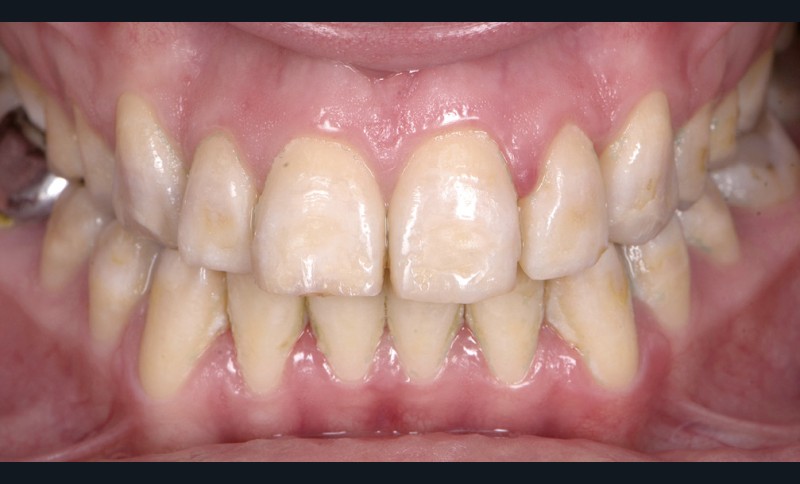

Dans tous les cas, le préjudice de l’enfant ou de l’adulte est non seulement fonctionnel – caractérisé par des sensibilités dentaires plus ou moins accrues, des malpositions occlusales associées parfois à une perte de dimension verticale – mais aussi esthétique, par l’aspect plus ou moins coloré et malformé des dents (fig. 1a, b). Le retentissement psychologique est variable selon la sévérité de l’atteinte et l’environnement social, mais reste important, surtout dans l’enfance [3].